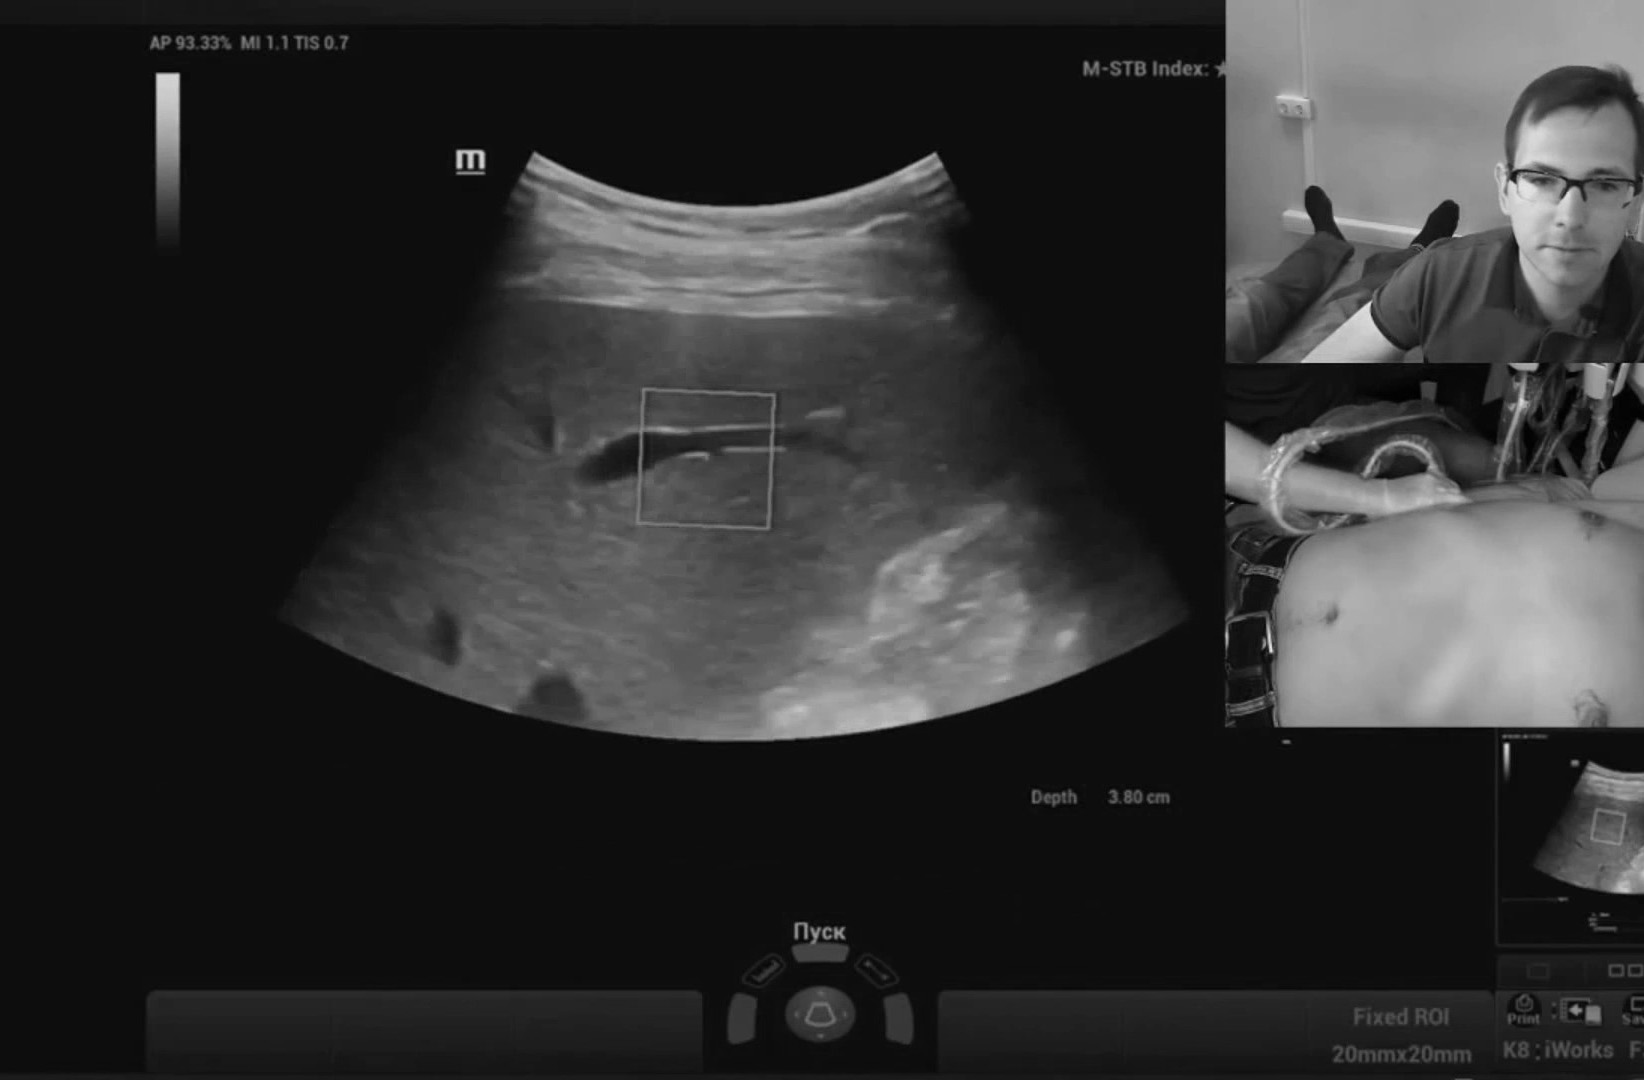

Обзор УЗИ: Отзыв о работе ультразвукового аппарата Mindray Resona 6

Работа с видео петлями реализована в полном объеме, то есть можно снять видео без оптимизации и отпустить пациента, оптимизацию провести уже на отснятых петлях в удобное время. Наличие эластографии сдвиговой волны периодически заставляет забыть, что я врач УЗД, бывают дни, когда делаешь одну эластографию печени. Очень популярная методика.